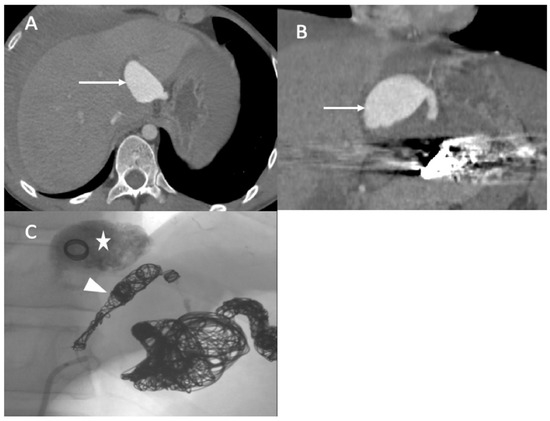

Figure 5.

(A,B) Axial and coronal abdominal CT images pertaining to the arterial phase show the aneurysm in the left hepatic artery (arrows) with perihepatic hematoma; (C) one coil was inserted in the aneurysm (star), and then glue and multiple coils were introduced into the common hepatic artery (arrowhead).